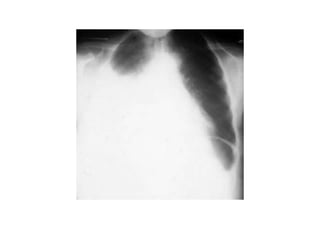

• Chest X-ray PA view showing dense

homogenous opacity at the Rt lung base with

curved upper border, blunting the

costophrenic angle and ascending towards the

axilla. Suggestive of Rt Pleural Effusion

• Around 200 mL of fluid is required in order for

it to be detectable on a PA chest X-ray.

Pleural Effusion

• Figure 10.17

• Chest X-ray showing a

large left pleural effusion

in a young man with a 4-

month history of malaise,

fever, night sweats and

weight loss. The diagnosis

of tuberculosis was

confirmed on histology of

a pleural biopsy and

culture of the pleural

fluid.